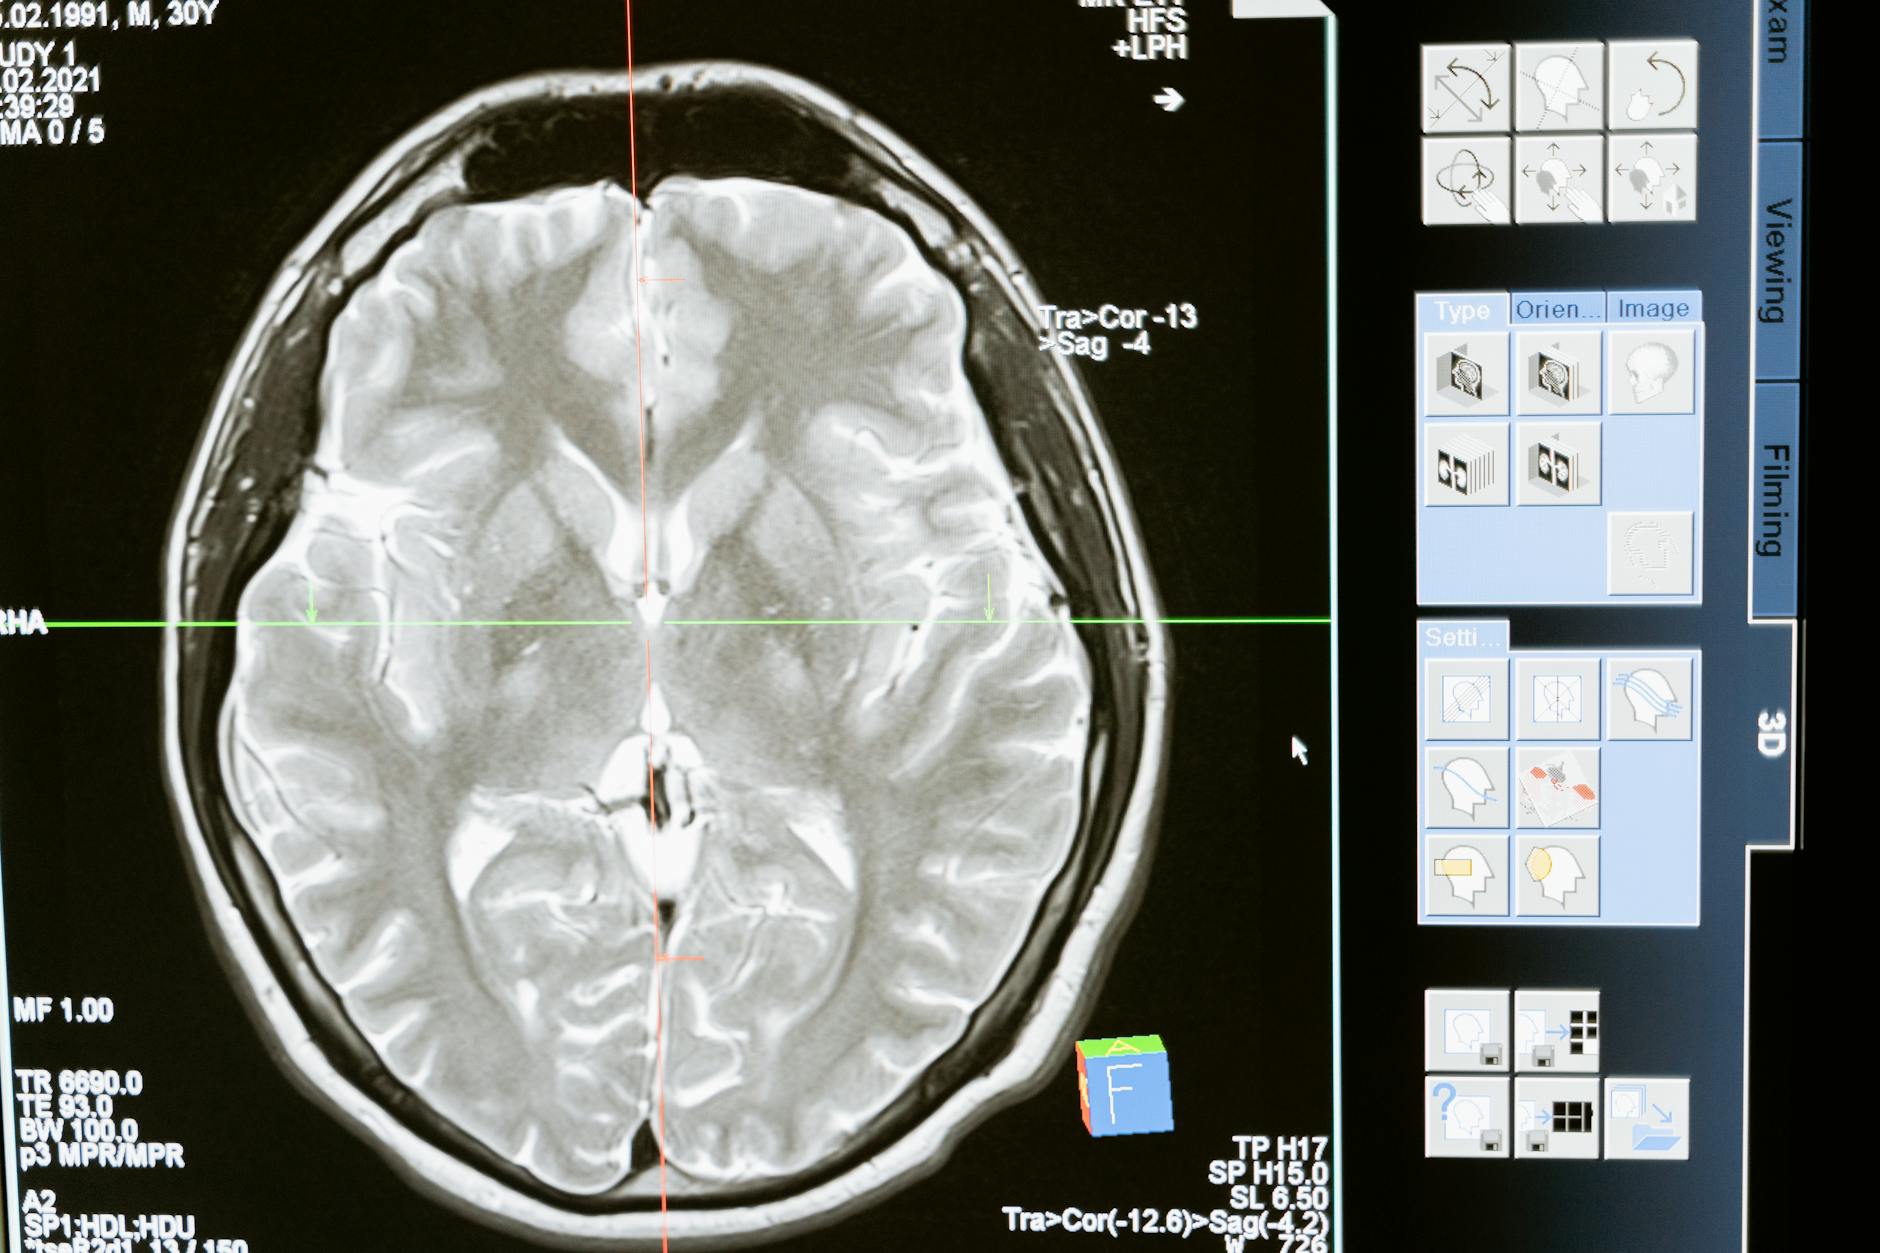

Um novo modelo de inteligência artificial para detecção de metástases cerebrais em ressonância magnética alcançou performance superior à dos radiologistas em velocidade e sensibilidade, segundo pesquisa divulgada pelo AuntMinnie. O modelo, desenvolvido com técnicas de deep learning treinadas em grandes coortes de pacientes oncológicos, é capaz de identificar lesões metastáticas cerebrais — incluindo micrometástases de difícil visualização — com maior consistência e menor taxa de erros de omissão do que a interpretação humana isolada.

O modelo reportado pelo AuntMinnie utiliza arquitetura de redes neurais convolucionais 3D treinadas em sequências de RM pós-contraste (T1 com gadolínio), que é a sequência padrão para avaliação de metástases. O treinamento incluiu milhares de estudos com anotações de especialistas neuroradiologistas, permitindo ao modelo aprender os padrões morfológicos e de sinal que caracterizam lesões metastáticas versus outras etiologias.